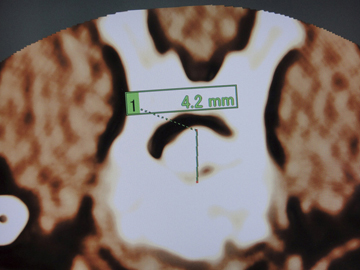

三次元CT検査は,手術計画を立てるにあたり,脊柱管内に逸脱した変性椎間板物質の詳細な情報を得るのに最良の検査方法の一つである。矢状断像での頭尾側方向への変性椎間板物質拡散範囲(図1),横断像での変性椎間板物質の左右方向への逸脱割合(図2),脊柱管背側方向への変性椎間板物質拡散範囲(図3),変性椎間板物質最大逸脱部位における脊髄圧迫の程度(図4),仮想内視鏡像での逸脱変性椎間板物質の形状(図5〜7)など多くの情報が得られる。

![]() 図4 変性椎間板物質最大逸脱部位における脊髄圧迫の程度 |